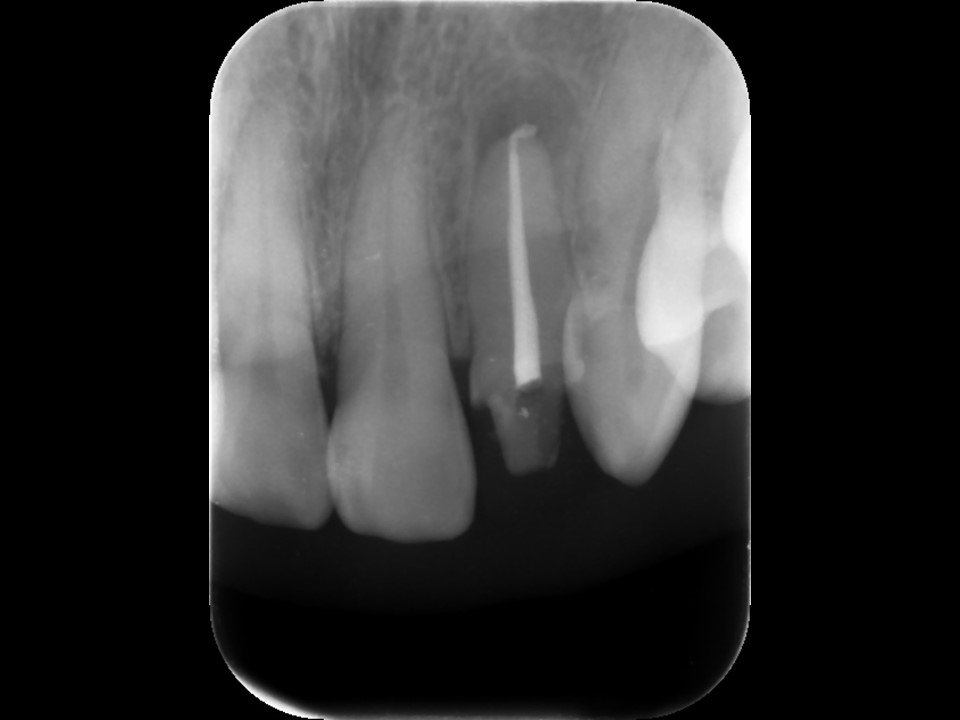

初診時レントゲン。根管充填がプアなため、根尖病巣を生じている。まずは再根管治療が必要と判断。たとえ高価な被せ物を被せても、根管治療に問題があると、いずれ再治療を行うか、いずれ抜歯になることに注意が必要。